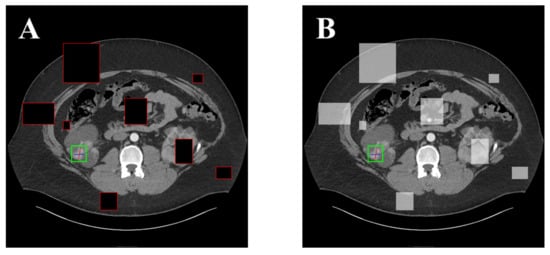

Furthermore, to prevent overfitting of the network, we undertake a random erase operation on image data before they are sent to the backbone network. This method’s function is similar to the dropout function []. Because the portion and location erased are random for every round of training, the network’s robustness can be improved, and the erased section can be considered as the blocked or distorted portion. Filling pixels with a predetermined color, such as black, or filling with the RGB channel mean of all pixels in the erased region are the two options for processing the erased section. The above-mentioned effects are depicted in Figure 2.

Figure 2.

Examples of two types of CutOut fillings. (A) Filling with black pixels; (B) Filling with the average of surrounding pixels in the erased portion.